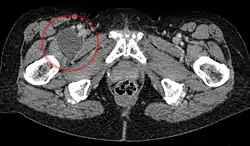

Iliopectineal bursa

Enlarged iliopectineal bursa in CT - scan

The iliopectineal bursa or the iliopsoas bursa is a large synovial bursa that separates the external surface of the hip joint capsule from the normally just the tendon of the iliopsoas muscle.[1]

The most proximal of part the iliopectineal bursa lies on the iliopubic eminence of the superior pubic ramus. The iliopectineal bursa passes across the front of the capsule of the hip joint and extends distally downwards almost as far as to the lesser trochanter.[2]

The iliopectineal bursa frequently communicates by a circular aperture with the cavity of the hip joint.[1]